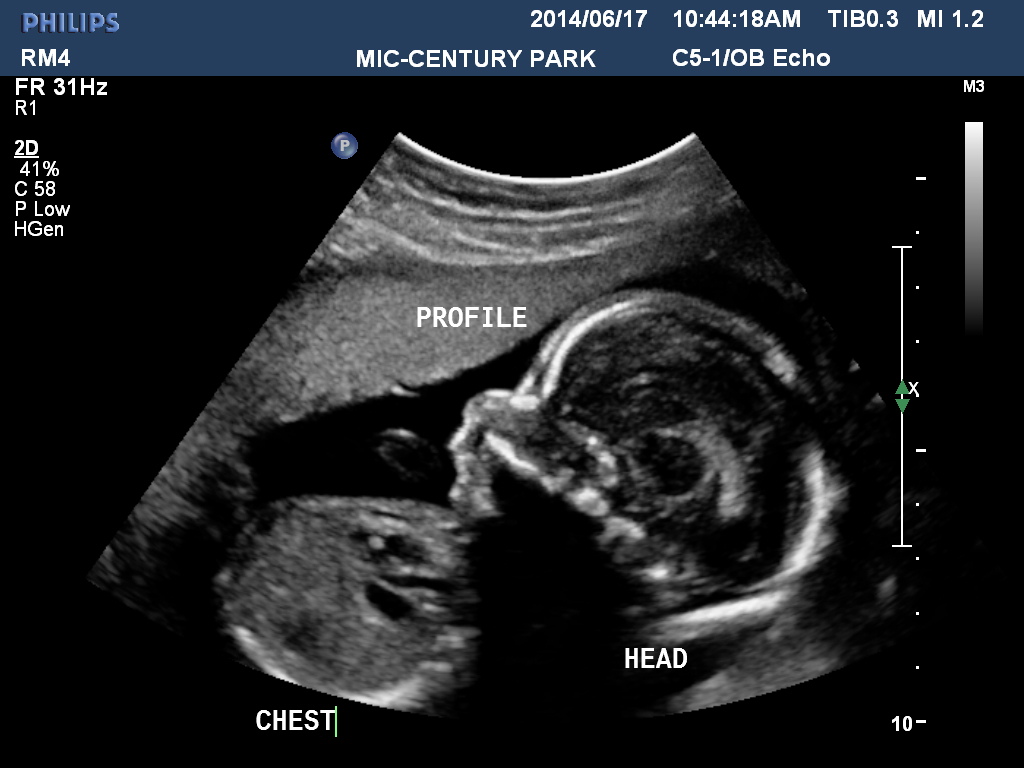

I went for my anatomy scan at 20 w 4 d. I did not ask the tech then about the gender however now i am very anxious! I haven't got that many pics but heres one. Not sure if it will be clear enough.Attachment 19533Attachment 19534